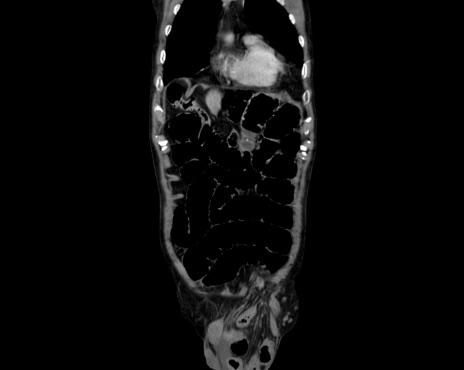

症例26(冠状断像)

【症例】80歳代男性

【主訴】嘔吐

【現病歴】昨晩2回嘔吐あり、今朝になっても嘔吐あり。来院。

【既往歴】胃潰瘍

【身体所見】意識清明、BT 37.6℃、BP 166/95mmHg、HR 100bpm、SpO2 97%、腹部:平坦・軟、腸蠕動音聴取良好、圧痛なし。

【データ】WBC 21900、CRP 1.4